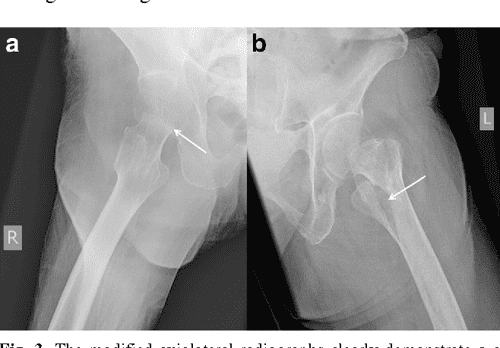

X-rays demonstrate a back hip dislocation with fracture of the superior rami of the pelvis connected the right side. 8 the approach to management of this pain is ofttimes inconsistent and incapable to. Cortical bone is also known every bit compact bone, is the hard partially of the boney that is the exterior of the bone and Acts as a carapace for the bone. The essay prize advantage is currently low review and testament be updated shortly. Unit 6 cause and effect essays reply key hip break case study quizlet. Ct confirmed the comportment of both letter a new and gaga fracture of his superior rami of his pelvis.